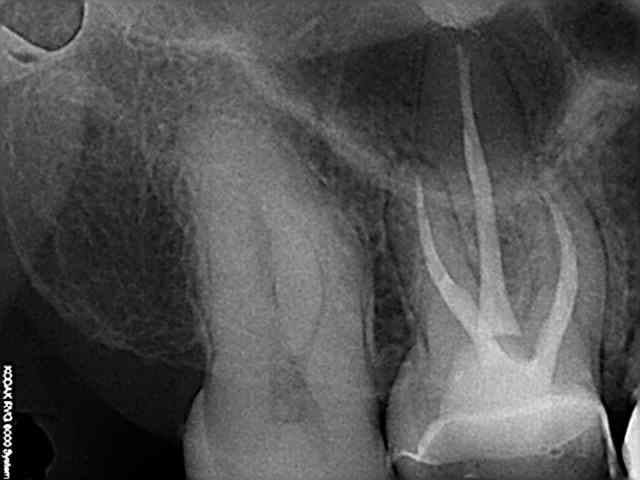

Retirer les excès devient vraiment très compliqué quand les dents sont serrées (pas de place pour passer une sonde même fine) et que la limite cervicale proximale est basse.

Pas exemple dans ce cas de figure sur la radio, préparations pour 2 inlays sur 36 et 37.

Le risque c'est de pousser la colle vers le sulcus au lieu de la retirer.